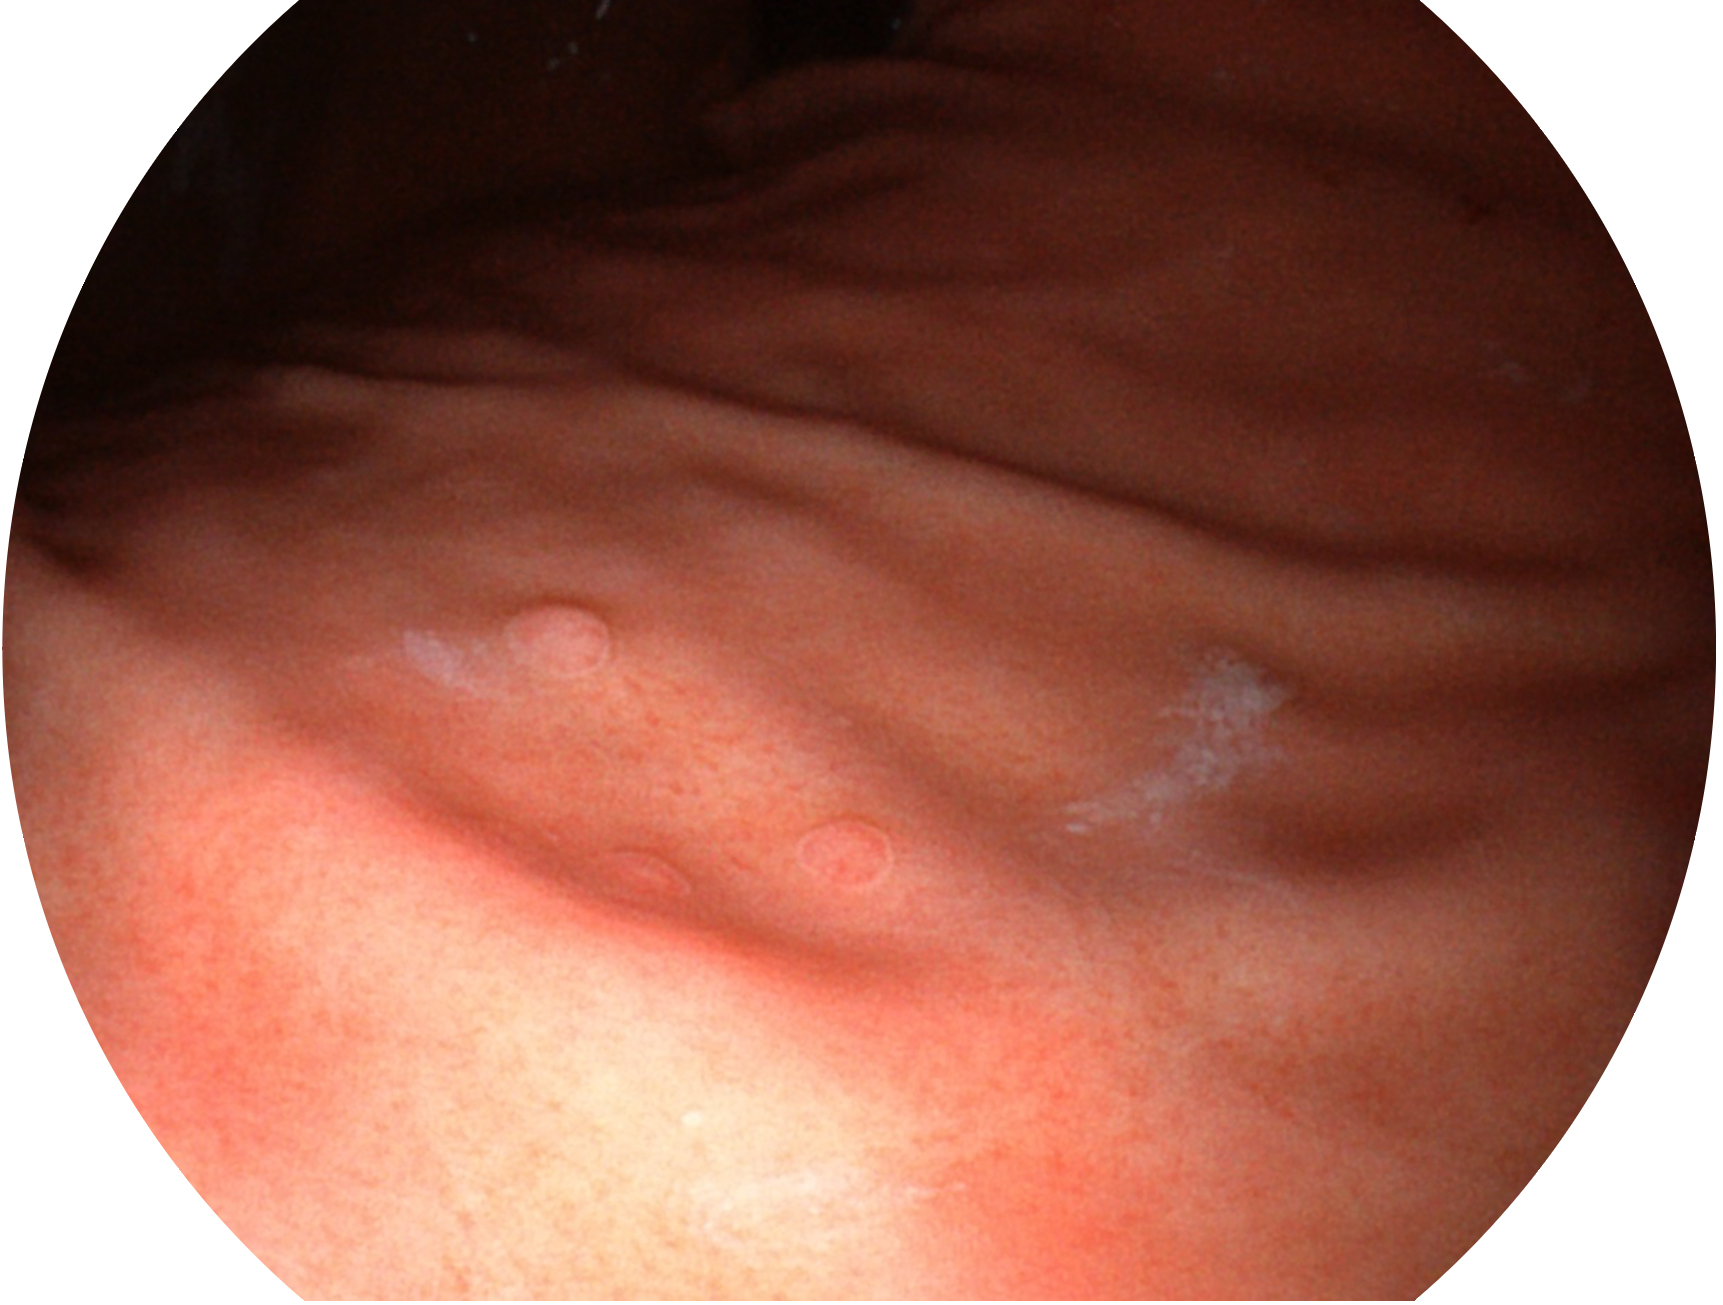

• 白光圖像 SFI圖像